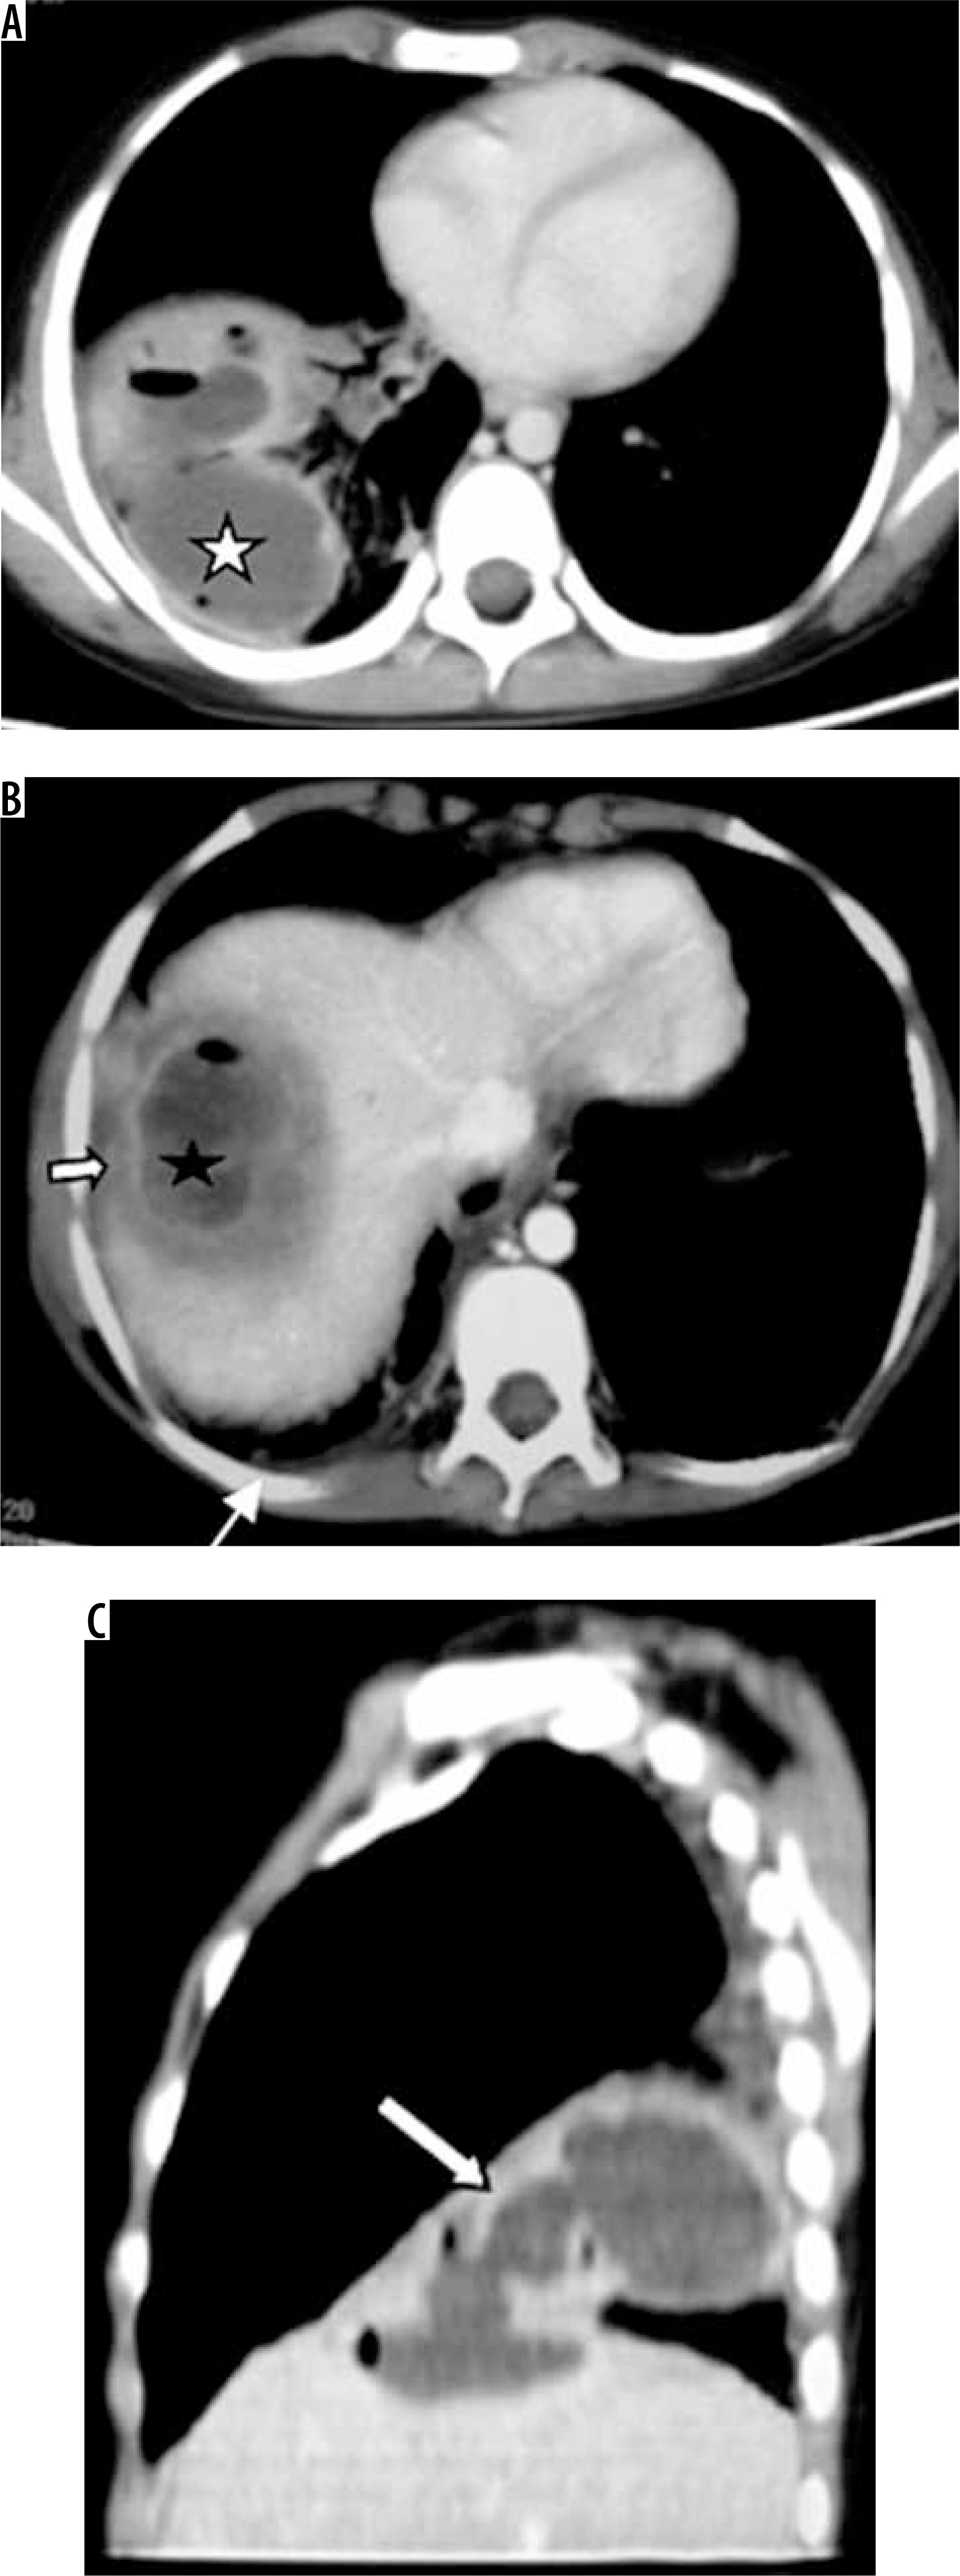

Figure 10

Patient with pain in the abdomen and fever. Diagnosed as amoebic liver abscess. A) Chest computed tomography (CT), shows presence of hypodense lesion with air fluid level in right lower lobe (white asterisk). B) Chest CT shows presence of hypodense lesion with shaggy walls in right lobe of liver with few air foci consistent with liver abscess (black asterisk). Note mild perihepatic fluid (white short block arrow) and minimal right pleural effusion (white thin arrow). C) Chest CT sagittal reformatted image, showing communication of liver abscess with lung abscess (white long block arrow)